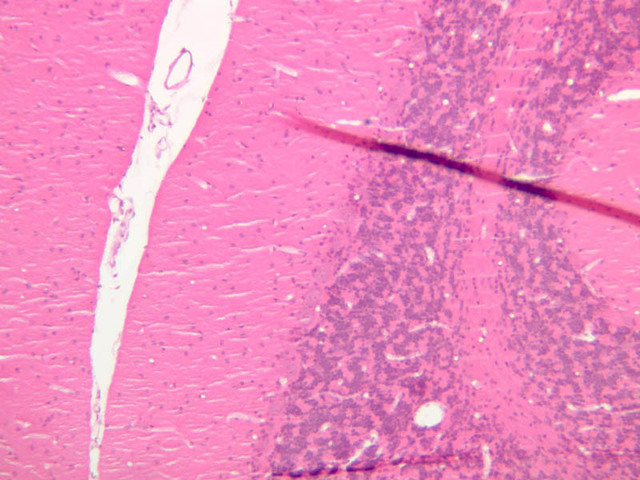

Examine the sections on slide A-85 with the unaided eye. Find the gray matter located within the interior of the cord (it has a "butterfly" shape). Examine the cresyl violet (CV) stained section first (the bluer one). Find the ventral horn under the microscope and locate the cell bodies of the large motor neurons (A-85, CV [1x] [2.5x-labeled, 10x, 20x, 40x] [2.5x, 10x, 20x, 40x-labeled]; H&E [1x] [2.5x-labeled, 10x, 20x, 40x-labeled]). Motor neurons are among the largest cells in the nervous system, particularly when their long processes are considered. Once again, note the large nucleus, the prominent nucleolus, and the clumps of darkly stained Nissl bodies. Look for neuronal processes – these will not be stained well with the cresyl violet stain (what does this tell you?). Dendrites are numerous and exit the cell as thick trunks that branch extensively. The axon hillock may also be seen as a thick trunk exiting the cell body, but this does not contain Nissl bodies as the dendrites do. Next, examine the dorsal horn (CV [2.5x, 10x, 20x, 40x]) and compare it to the ventral horn. Also examine the white matter (CV [2.5x, 10x, 20x, 40x]; H&E [2.5x, 10x, 20x, 40x-labeled]). Axons are more difficult to identify because they exit the soma as thin processes, and the irregular course they take makes them difficult to follow in sections. The term neuropil refers to the complex, felt-like net of axonal, dendritic, and glial arborizations that form the bulk of the gray matter of the CNS and in which the nerve cell bodies are embedded. To appreciate the complex wiring of the CNS, examine slide A-83 (Sevier Ag [2.5x, 10x, 20x, 40x]), which is a section from the brainstem stained using a silver impregnation technique.

A85, Spinal Cord (Ventral Horn), 1x (CV) A85, Spinal Cord (Ventral Horn), 2.5x (CV) A85, Spinal Cord (Ventral Horn), 10x (CV) A85, Spinal Cord (Ventral Horn), 20x (CV) A85, Spinal Cord (Ventral Horn), 40x (CV) A85, Spinal Cord (Ventral Horn), 2.5x (CV) A85, Spinal Cord (Ventral Horn), 10x (CV) A85, Spinal Cord (Ventral Horn), 20x (CV) A85, Spinal Cord (Ventral Horn), 40x Labeled (CV) A85, Spinal Cord (Ventral Horn), 1x (H&E) A85, Spinal Cord (Ventral Horn), 2.5x Labeled (H&E) A85, Spinal Cord (Ventral Horn), 10x (H&E) A85, Spinal Cord (Ventral Horn), 20x (H&E) A85, Spinal Cord (Ventral Horn), 40x Labeled (H&E) A85, Spinal Cord (Dorsal Horn), 2.5x (CV) A85, Spinal Cord (Dorsal Horn), 10x (CV) A85, Spinal Cord (Dorsal Horn), 20x (CV) A85, Spinal Cord (Dorsal Horn), 40x (CV) A85, Spinal Cord (White Matter), 2.5x (CV) A85, Spinal Cord (White Matter), 10x (CV) A85, Spinal Cord (White Matter), 20x (CV) A85, Spinal Cord (White Matter), 40x (CV) A85, Spinal Cord (White Matter), 2.5x (H&E) A85, Spinal Cord (White Matter), 10x (H&E) A85, Spinal Cord (White Matter), 20x (H&E) A85, Spinal Cord (White Matter), 40x Labeled (H&E) A83, Brainstem, 2.5x (Sevier Ag) A83, Brainstem, 10x (Sevier Ag) A83, Brainstem, 20x (Sevier Ag) A83, Brainstem, 40x (Sevier Ag)

Spinal Cord Table of Identifications

Row Structure Abbreviation Optimal Stain Representative Section Note

1 Dendrite (arrow) H&E, CV a85 gray matter spinal cord 40x labeled.jpgA85, Spinal Cord (Ventral Horn), 40x ; a85b ventral horn gray matter spinal cord 40x cv labeled.jpgA85, Spinal Cord (Ventral Horn), 40x

2 Nissl Bodies (arrows) H&E, CV a85 gray matter spinal cord 40x labeled.jpgA85, Spinal Cord (Ventral Horn), 40x ; a85b ventral horn gray matter spinal cord 40x cv labeled.jpgA85, Spinal Cord (Ventral Horn), 40x

3 Nucleus (arrow), (outline) H&E, CV a85 gray matter spinal cord 40x labeled.jpgA85, Spinal Cord (Ventral Horn), 40x ; a85b ventral horn gray matter spinal cord 40x cv labeled.jpgA85, Spinal Cord (Ventral Horn), 40x

4 Nucleolus (arrow) H&E, CV a85 gray matter spinal cord 40x labeled.jpgA85, Spinal Cord (Ventral Horn), 40x ; a85b ventral horn gray matter spinal cord 40x cv labeled.jpgA85, Spinal Cord (Ventral Horn), 40x

5 Motor Neuron Cell Body (none), (arrow) H&E, CV a85 gray matter spinal cord 40x labeled.jpgA85, Spinal Cord (Ventral Horn), 40x ; a85b ventral horn gray matter spinal cord 40x cv labeled.jpgA85, Spinal Cord (Ventral Horn), 40x

6 Neuroglia (arrows) CV a85b ventral horn gray matter spinal cord 40x cv labeled.jpgA85, Spinal Cord (Ventral Horn), 40x

7 White Matter (none) CV a85 ventral horn gray matter spinal cord 2x cv labeled.jpgA85, Spinal Cord, 2.5x

8 Gray Matter (none) CV a85 ventral horn gray matter spinal cord 2x cv labeled.jpgA85, Spinal Cord, 2.5x

9 Dorsal Horn (none) CV a85 ventral horn gray matter spinal cord 2x cv labeled.jpgA85, Spinal Cord, 2.5x

10 Ventral Horn (none) CV a85 ventral horn gray matter spinal cord 2x cv labeled.jpgA85, Spinal Cord, 2.5x